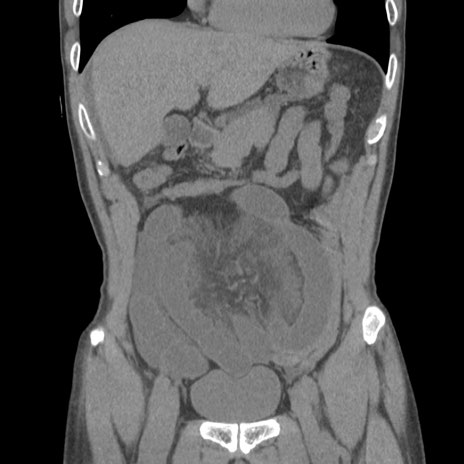

症例56 CT(冠状断像)

横断像